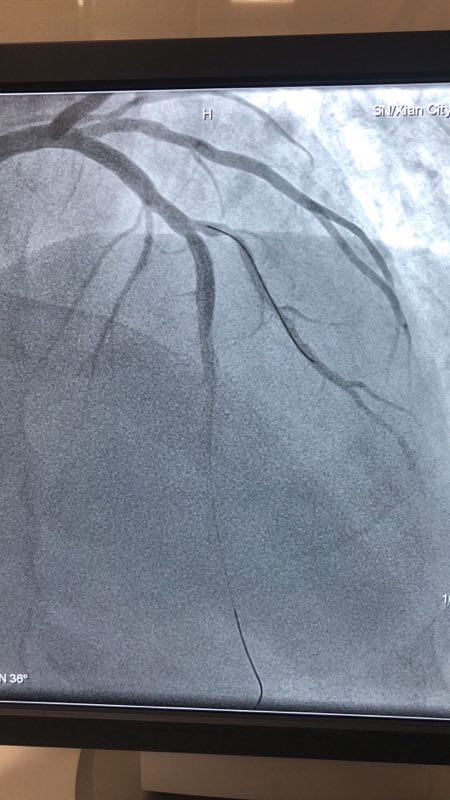

此例患者,男性,56岁,11年前因心绞痛在西京医院行冠状动脉造影检查后于D1对角支置入1枚支架治疗。术后患者口服“阿司匹林肠溶片、氯吡格雷、阿托伐他汀”等药物治疗1年后自行停药,并有长期大量吸烟史。2018年12月24日患者突发胸痛、胸闷,急来我院就诊。急诊行冠状动脉造影检查提示D1对角支原支架内再狭窄70%-90%。急救中心主任张誉洋副主任医师考虑到第一对角支管径较小,于原支架内再次置入支架引起再狭窄的风险极大,遂建议应用药物涂层球囊扩张术治疗D1对角支原支架内狭窄。与患者充分沟通后,于12月27日行冠脉药物涂层球囊PTCA术治疗,造影显示血管开通情况良好,术后患者症状明显改善。